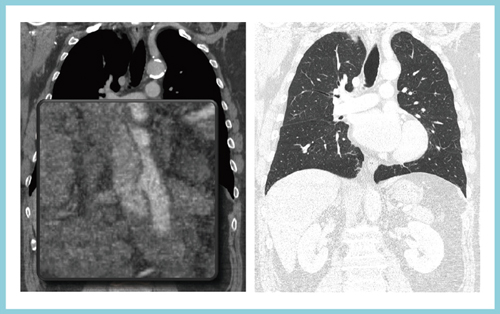

これによって,トリプルルールアウトと言われる,大動脈疾患と肺塞栓と冠動脈疾患を同時に撮影する造影CTをより広範囲に検査がすることが可能になる(図7)。さらに,管電流変調を工夫することで,従来のCTでは難しかった大動脈乖離の腎動脈のフラップの描出や,心臓の周囲の肺の評価などの臨床応用が可能になることが期待される。

図7 胸部造影CTによるトリプルルールアウト